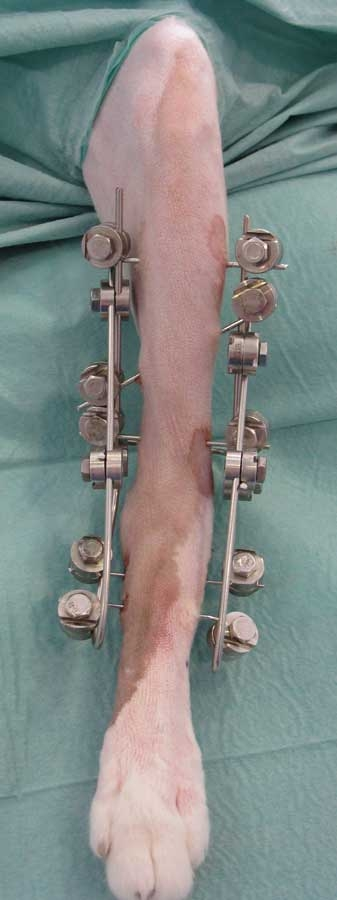

External fixators | Pins crossing the skin and bone, connected by bars outside | Maintain the stability of a bone or joint without fully opening the bone site. Avoid placing hardware in the contaminated area | Open fracture. Ankle sprain |

Criterion | Plates & screws | External fixators | Pins / nails |

Typical use | Diaphyseal fractures, osteotomies, TPLO, arthrodeses | Open, infected fractures, joint sprains | Simple or articular fractures |

Equipment | Lots of costly equipment: plates, screws, guides, drills, screwdrivers | Little equipment: pins, rods, clamps, tightening wrenches | Little equipment: smooth or threaded pins, pin cutter, cerclage wire |